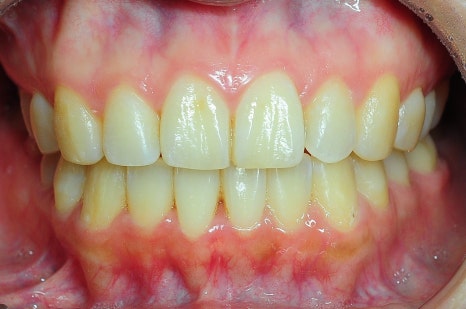

< 스마일디치과 비발치 교정 사례 >

*치료 전후 사진은 환자의 동의하에 게재하였으며, 동일한 환경과 조건에서 촬영된 전후 사진입니다.